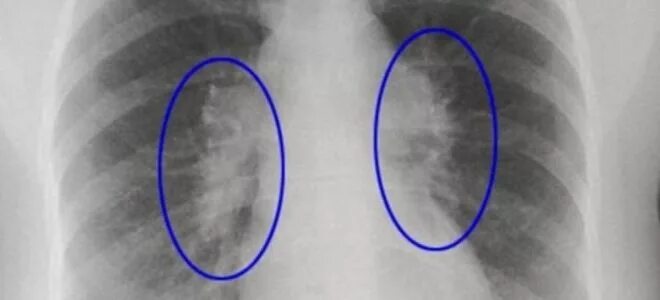

Фиброзное изменение левого легкого